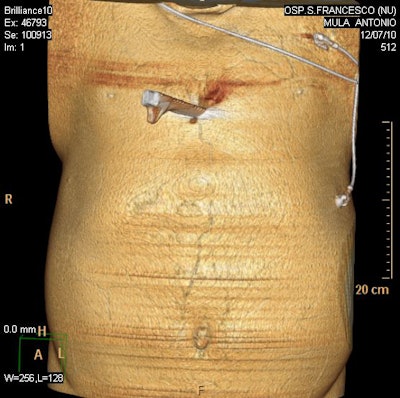

Because many stabbing victims die before reaching hospital it is vital the trauma team has as much information about the site of the wound(s) and can arrange to have the radiology team on standby or the use of a mobile machine depending on wound location, weapon, and ease of accessibility. Positioning patients may present a challenge as often the weapon remains in situ until it can be removed in a controlled surgical situation.

The radiological evaluation of penetrating knife injuries can be daunting given the emergency circumstances requiring imaging. The challenges facing the radiologist in imaging assessment of penetrating trauma impacts significantly on the effective management of these patients in the acute setting.